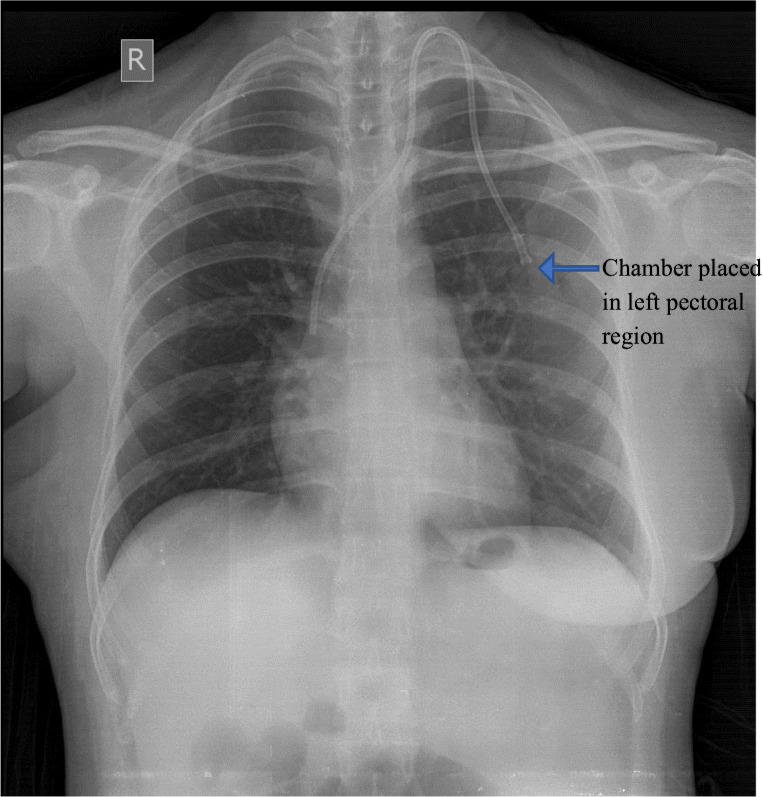

The chemoport insertion procedure was performed under general anesthesia in all cases. In all cases, we gained venous access through internal jugular vein. In 15 cases, we accessed the left internal jugular vein as they had undergone modified radical mastectomy on right side (Fig. 1). The reservoir was placed beneath the skin on the pectoral region, and catheter was tunneled through the subcutaneous plane into the internal jugular vein. The tip of the catheter was placed at the junction of superior vena cava and right atrium. We routinely use C-arm to confirm the position of the catheter tip. The port was used after 48 h of insertion in 87 cases. In 11 cases, the needle was inserted on-table, and the port was used for chemotherapy infusion after 24 h. We use the chemoport to administer chemotherapy only.

Fig. 1.

Showing placement of the port in the left pectoral region in an operated case of right side carcinoma breast